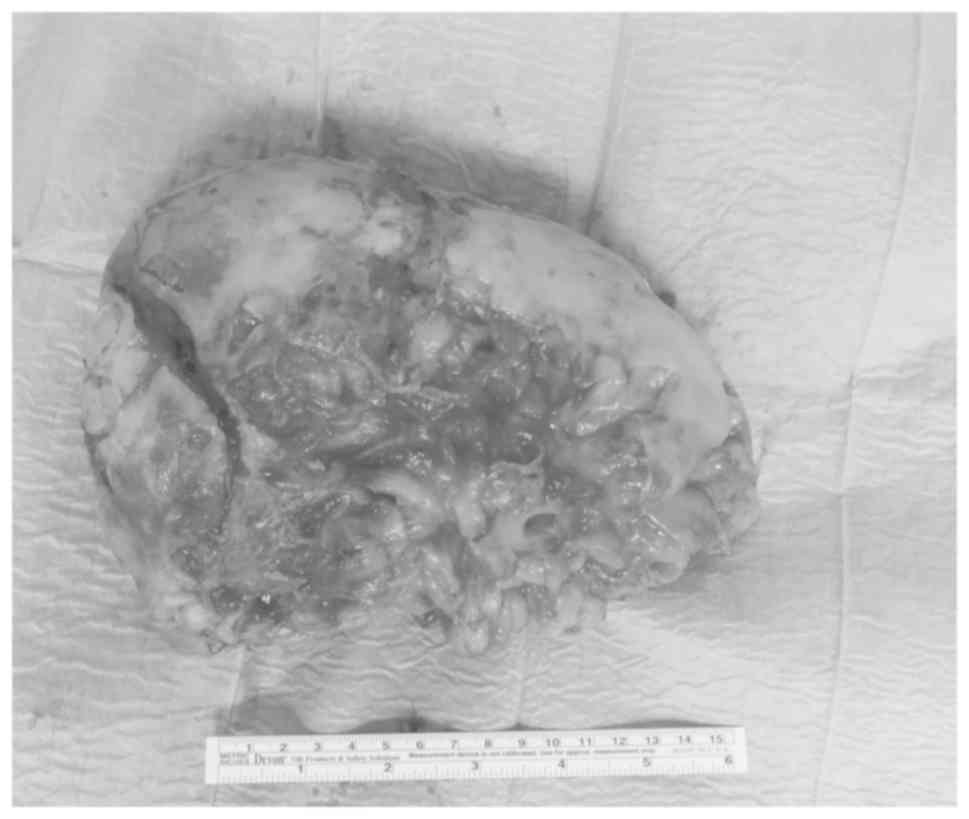

Adrenal myelolipoma is a rare mesenchymal tumour with benign biological behaviour that is mainly composed of mature adipose and myeloid tissue. Both sexes are equally affected, most commonly between the fifth and seventh decades of life. The diagnosis of adrenal myelolipoma is mostly incidental. Although it may occasionally be associated with necrosis, rupture and haemorrhage, causing abdominal pain, this tumour is usually asymptomatic. Consequently, management is conservative, while surgical treatment is reserved for symptomatic cases, or for masses growing quickly or to a size >6 cm. Giant myelolipomas (sized >10 cm) are rare. Open radical adrenalectomy is the standard treatment for giant myelolipomas, while the minimally invasive approach has been used in only few cases. We herein report the case of a patient with a giant adrenal myelolipoma who underwent robotic partial adrenalectomy. To the best of our knowledge, this is the largest giant adrenal myelolipoma treated with robotic surgery reported in the literature to date. A 55‑year‑old male patient underwent an abdominal computed tomography scan during follow‑up after radical prostatectomy for prostate cancer Gleason Score 6 (ISUP 1) due to biochemical recurrence. The examination revealed a right hypodense adrenal mass, sized 16x13 cm. Abdominal magnetic resonance imaging confirmed the presence of characteristics suggestive of a myelolipoma. The patient did not report any symptoms. Due to the benign characteristics of the mass, robotic partial adrenalectomy and enucleation of the mass were performed. The operative time and estimated blood loss were 205 min and 100 ml, respectively. No intra‑ or postoperative complications occurred. The patient was mobilized on the first postoperative day and the time to flatus was 36 h; the length of hospitalization was 4 days. Histological examination confirmed the diagnosis of adrenal myelolipoma, sized 18x11.5x6 cm. No tumour recurrence occurred over a follow‑up period of 12 months. In conclusion, robotic surgery allows performing partial adrenalectomy with a lower risk of bleeding and with preservation of healthy adrenal tissue, which is of paramount importance for the patient as it reduces recovery time and the need for medical substitution therapy.

Figure 1

Figure 2

Figure 3